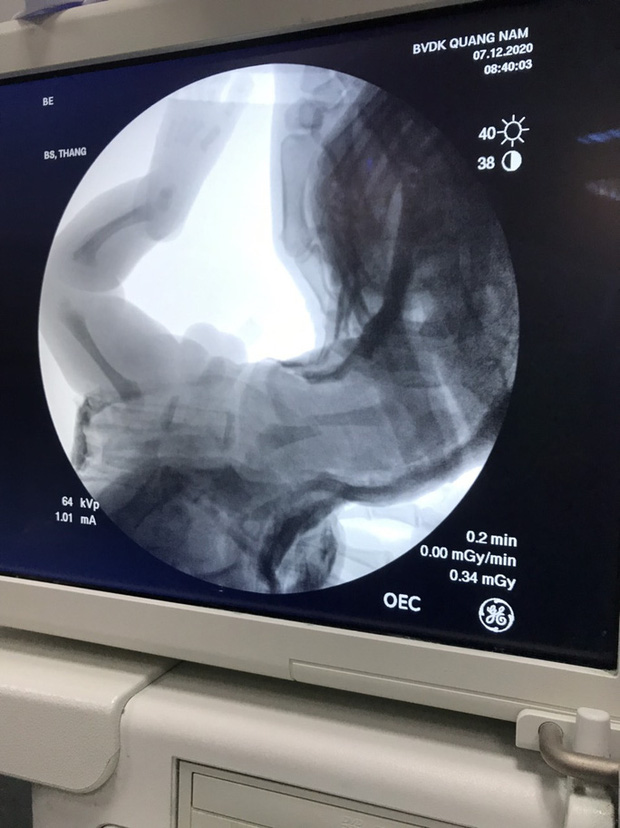

Cháu bé vừa chào đời đã bị gãy chân Ảnh: Sở Y tế Quảng Nam cung cấp

Sau đó, các bác sĩ đưa được cháu bé ra ngoài, cân nặng 3,1 kg. Báo cáo cho biết sau khi chào đời, phản xạ và hoạt động tay chân bé "không có biểu hiện bất thường". Mẹ và bé được bác sĩ, nữ hộ sinh khám, chăm sóc thường quy tại khu hậu phẫu thuật. Qua thăm khám, bác sĩ phát hiện vùng đùi trái của trẻ sưng nề nhẹ, không bầm tím. Kết quả chụp phim cho thấy cháu bé bị gãy xương đùi trái.

Sau khi xác định bé gãy xương, Khoa Phụ sản đã cùng Khoa Ngoại chấn thương thực hiện mổ, nắn bó bột chậu đùi bàn chân trái cho cháu bé.